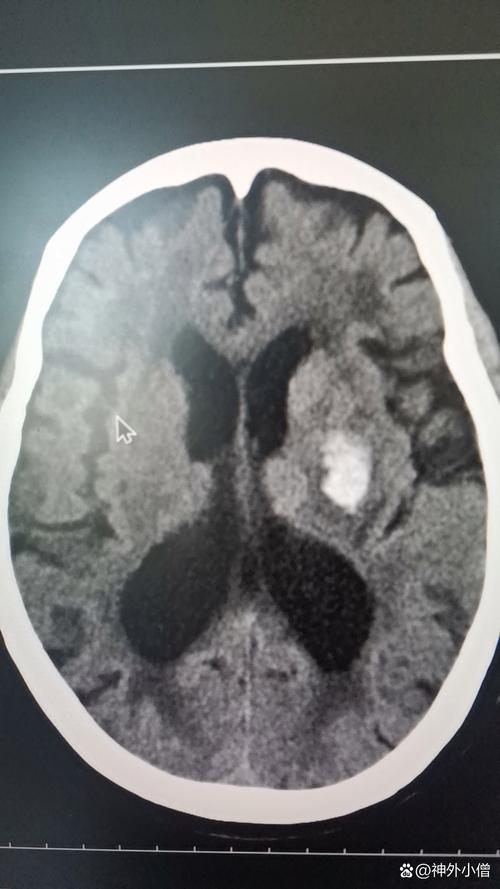

治疗脑梗:

(图片来源网络,侵删)- 如果在发病的极早期(如4.5小时内),且没有禁忌症,可能会考虑使用溶栓药物(如阿替普酶)来溶解堵塞血管的血栓,但在已经出血的情况下,这是绝对禁忌的。

- 后期治疗主要是改善侧支循环、营养神经、预防并发症等。